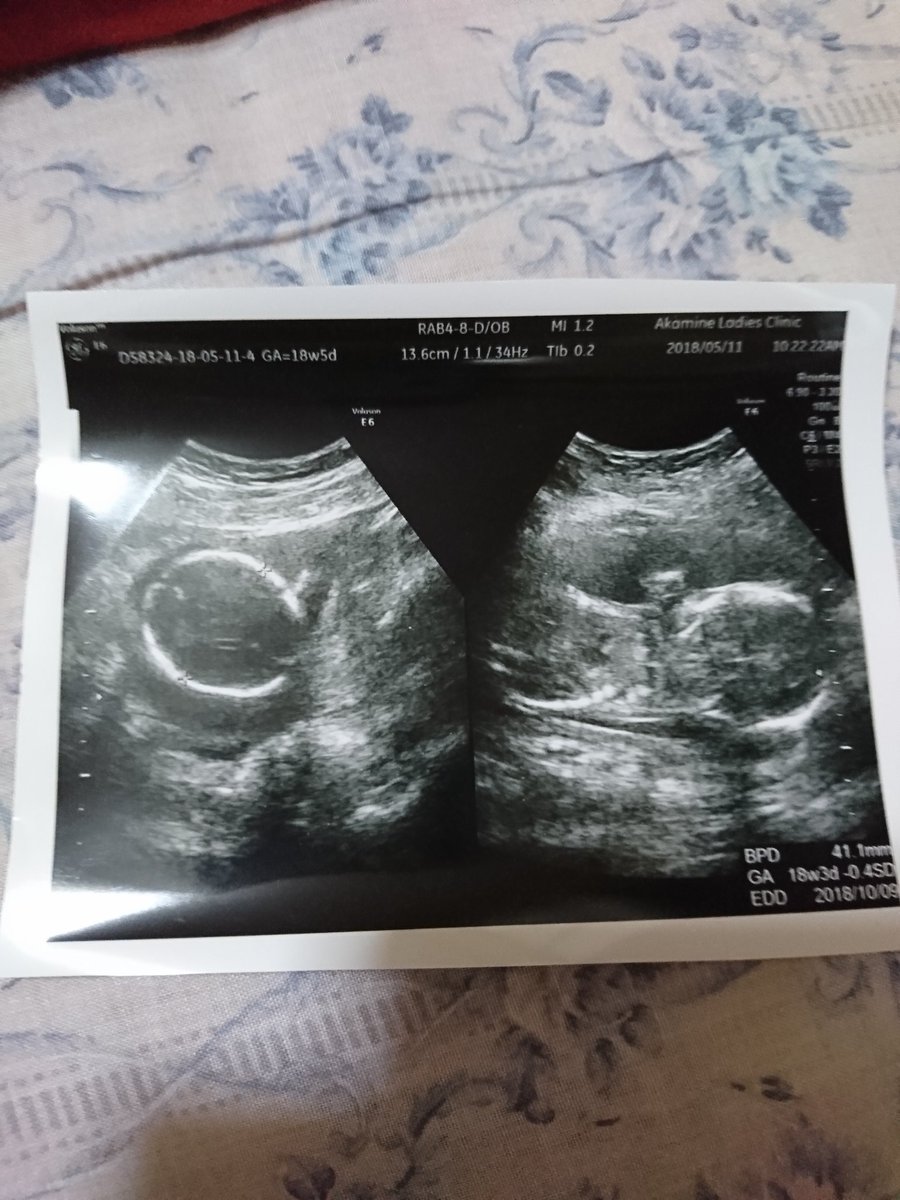

18週1日 洋梨サイズに 流産3回からの46歳高齢出産へ

18週2日 切迫流産で入院 退院しました 共働き夫婦の育児記録 2018 10月息子出産

妊娠 流産 早産 出産 体験日記 18週1日 昨日の健診結果と性別は

妊娠18週目 赤ちゃんの胎動に気づき始める頃 流産の確率は軽減 L4mama エル フォー ママ

妊娠18週目の現状報告と振り返り 流産回避の妊娠初期編 アラフォーリアル妊活日記